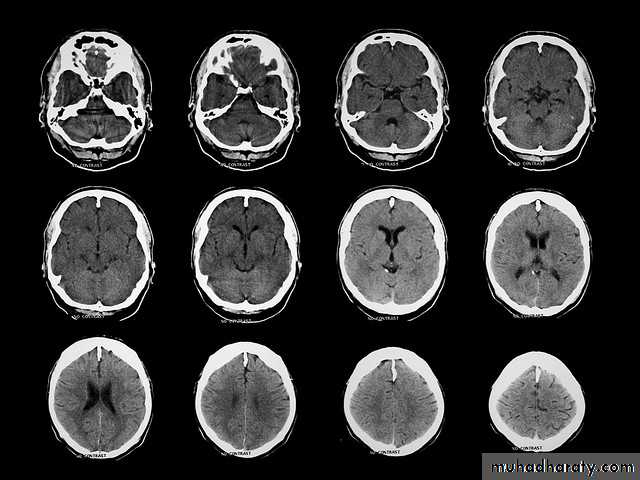

Common CT findings of traumatic brain injury